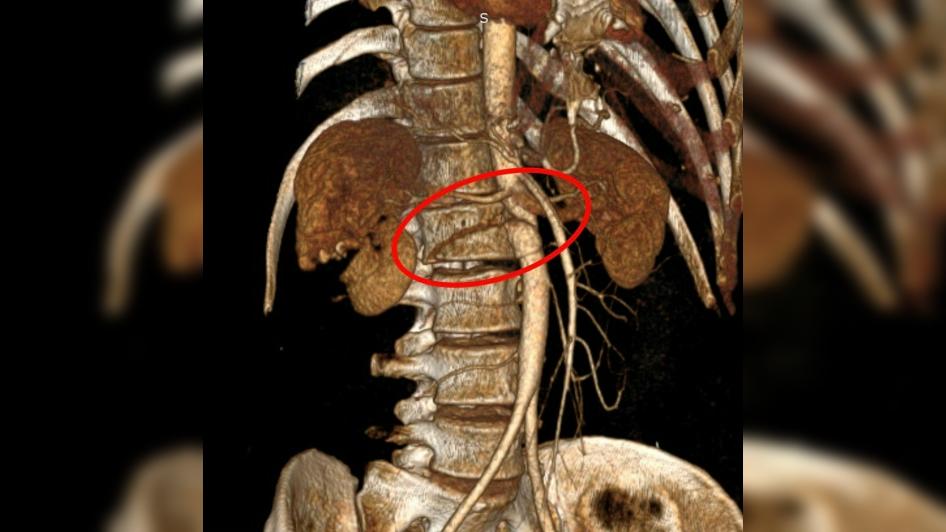

После госпитализации у пациента обнаружили массивную забрюшинную гематому, разрыв инфраренального отдела брюшной аорты, повреждение правой почки и поджелудочной железы.

Фото: пресс-служба НИИ им. Джанелидзе

Чтобы спасти человека, врачи провели экстренную операцию. Во время неё медики удалили почку с правой стороны, зашили разрыв брюшной аорты и перевязали повреждённые поясничные артерии.